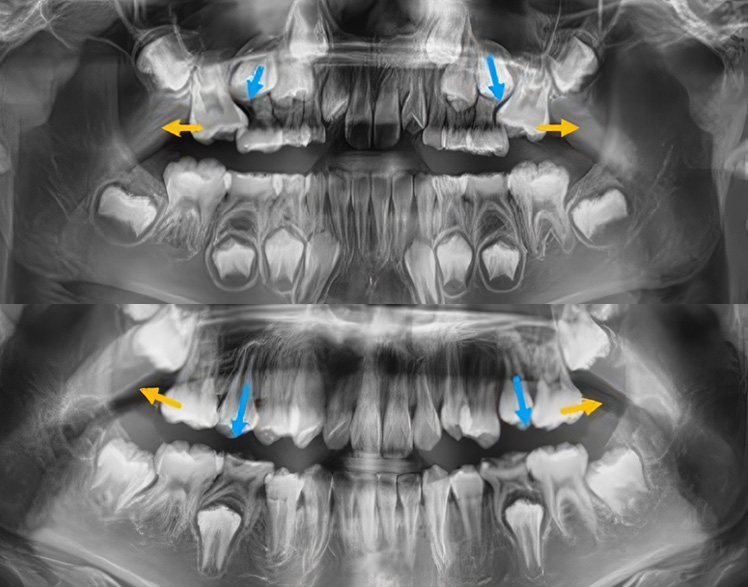

쓰러진 어금니 세우기

어린이 예방교정

공간 관리를 통해 건강한 치열 만들기

유치가 일찍 빠지거나 충치때문에 쓰러진 어금니를 바로 세우고, 영구치의 자연스러운 맹출을 유도합니다.

Impacted Tooth

숨어있는 치아교정,

매복치

매복치아나 늦게 나오는 치아 때문에 걱정되시나요?

교정치료를 통해 숨어있는 치아가 자연스럽게 나올 수 있도록 도와드립니다.

아이의 건강한 치아 배열을 위해 적절한 시기에 시작하세요.